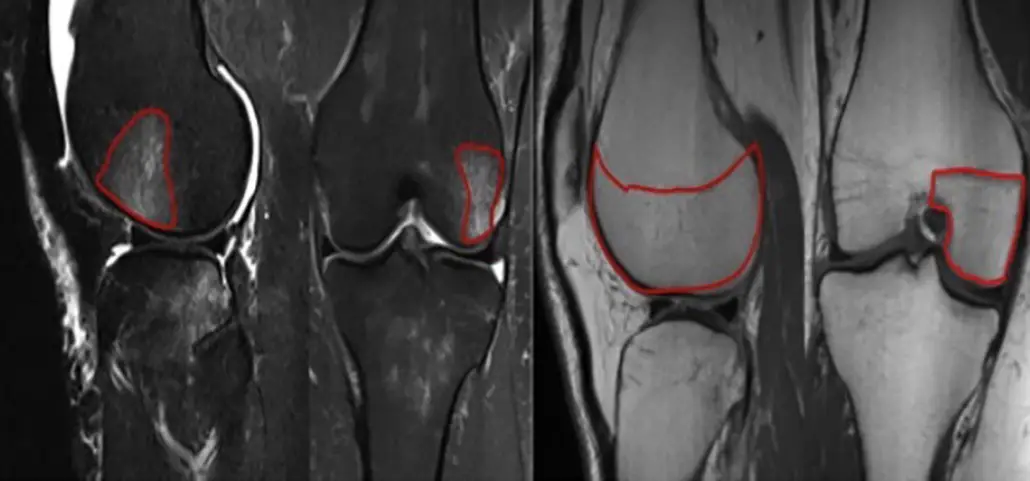

In this study, the authors looked at the incidence of radiographic chondral changes (without correlation with clinical and functional outcomes) on MRI 5 years after the ACL tear.

Bone bruises often coincide with an acute ACL tear and can be seen on an MRI. Basically, a larger bone bruise was shown to have a significant influence on chondral changes 5 years post-surgery.

In most of the cases, the lateral side of the knee (both the tibia and the femur) were involved. Whereas the medial side had fewer incidences of a bone bruise after the injury.